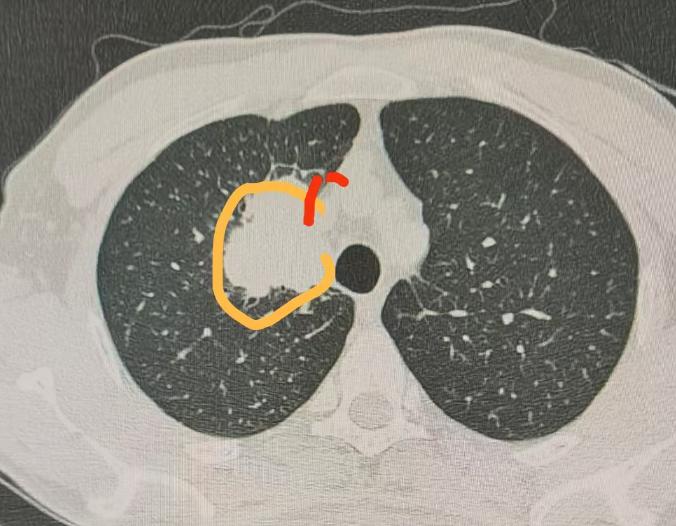

刚完成一台右上肺癌手术,这位患者一周前,曾在外院接受过肺癌手术,但因为术中医生发现肿瘤侵犯上腔静脉,所以手术就没给他做成。 经过我对患者影像资料的详细分析,PET-CT显示无淋巴结转移,奇静脉弓区域较为干净,肺动脉主干状态尚可。 问题的关键在于肿瘤与上腔静脉紧密粘连,侵犯严重,导致手术难以进行。但在纵隔窗影像中可见,侵犯范围较为局限,仅集中于上腔静脉局部区域。 尽管肿瘤与血管粘连紧密,但肺动脉主干以下部分未受侵犯,且全身未见转移。此外,右肺中叶的结节经判断为结核性,不影响手术决策。 综合考虑,患者仍有望通过手术获益,且病灶靠近上腔静脉,活检难度大,风险高,因此多数医生不愿进行穿刺。 今日我为患者实施了开胸手术,切口约15cm。术中控制上腔静脉的远端与近端,确保操作安全。 随后完成右上肺切除,并对受侵犯的上腔静脉侧壁进行切除与吻合,手术过程顺利,出血控制良好。 这一案例提示我们,在肿瘤治疗中,不应一味追求微创。虽然微创手术创伤小、恢复快是重要目标,但实现肿瘤的彻底切除与手术安全更为关键! 此次手术虽切口较长,但在大血管控制到位的前提下,出血极少,整体效果理想。[作揖][玫瑰]